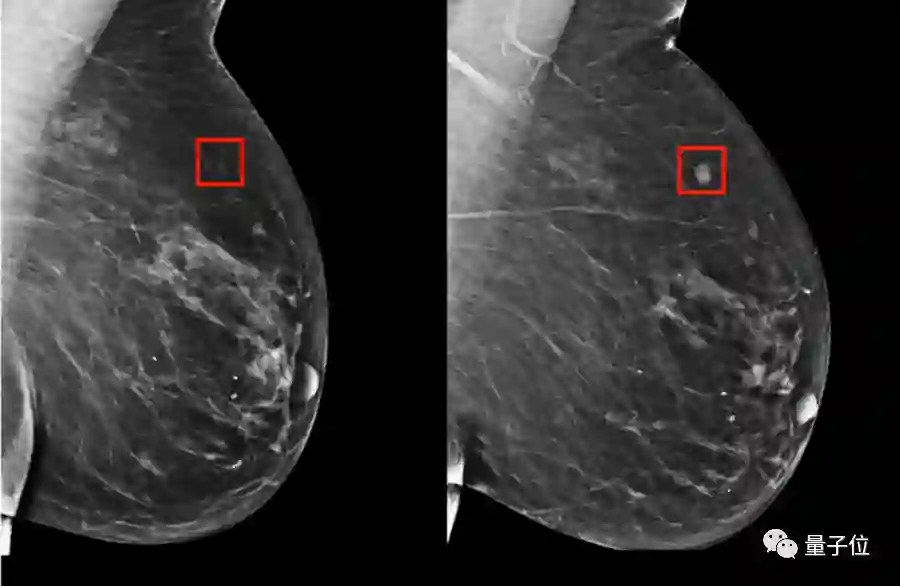

第二个是仅基于X光片图像的深度学习模型;用PyTorch构建了一个深度卷积神经网络ResNet。给定一个乳房的1664 X 2048像素图片,模型会预测是否会在5年内发展成乳腺癌。

最后一种是结合RF-LR和X光片的混合模型,这也是最终投入临床使用,准确率最高的模型。

在临床对比中,在已确诊的乳腺癌患者中,混合模型在前期就对其中的31%作出了预警,而传统的TC模型的有效预警仅有18%